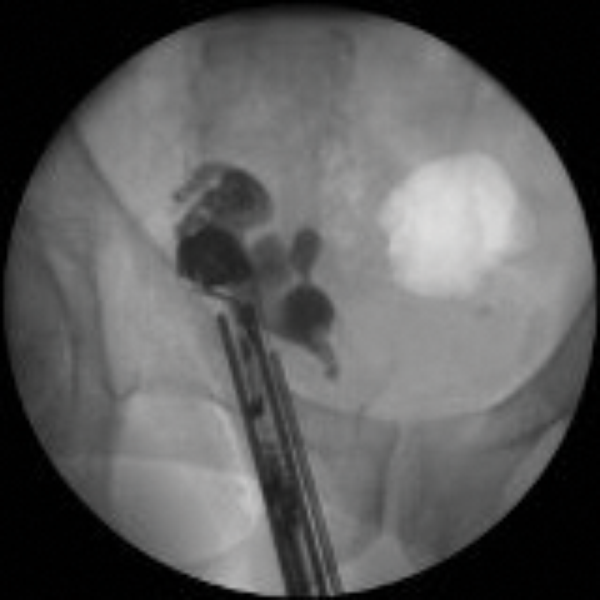

Occasionally, interventional imaging of the seminal vesicles is required to exclude anatomical abnormalities. One approach is with a vesiculoscope and retrograde imaging via catheterisation of the ejaculatory ducts. Another approach is antegrade imaging of the seminal vesicles after a TRUS guided injection of contrast referred to as seminal vesiculography (Figure 2).

Figure 2: Antegrade seminal vesiculoscopy showing a stone close to the right ejaculatory duct.